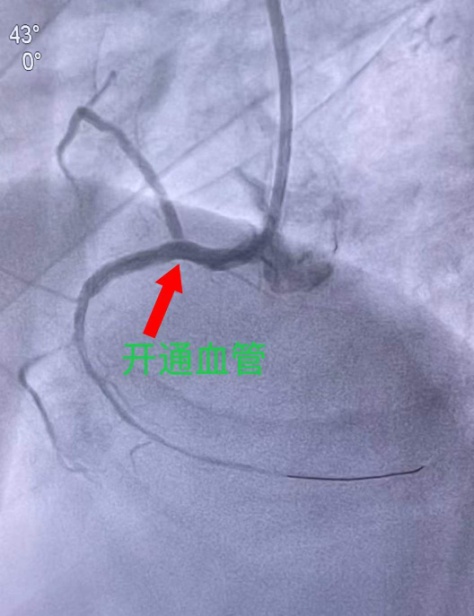

崔迎辉医生采用右侧桡动脉入路,在金星医生协助下为患者行冠脉造影术,造影显示患者的右冠状动脉近段完全闭塞,更换指引导管,操作导丝通过闭塞段血管,经指引导管缓慢注入尿激酶原溶栓,随后沿导丝送入球囊扩张病变处,最后于右冠状动脉近段植入一枚药物支架,解决了右冠状动脉的病变问题,血流恢复正常。

手术过程中患者仍反复出现室颤,危急时刻,手术团队沉着冷静,及时给予心脏电除颤,以最快的速度开通闭塞血管,整个手术仅用时38分钟,经过争分夺秒的抢救和手术,为患者开启了“生命之门”,术后将患者送入ICU进一步治疗,并与ICU彭育昕医生共同制定术后治疗方案,患者心律、血压等平稳后,转回CCU继续治疗。